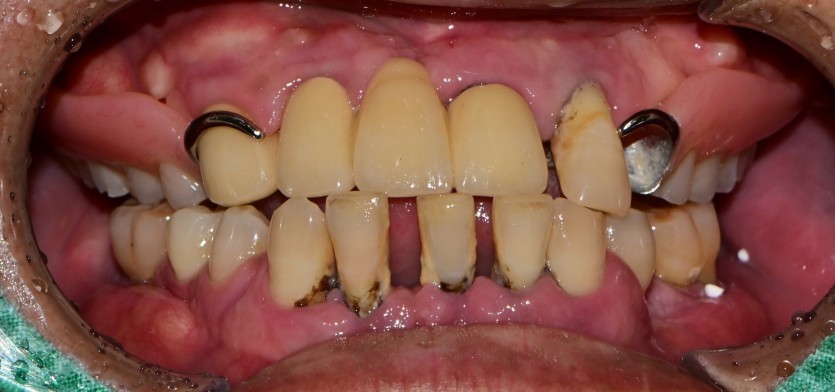

만 52세 전악 상악, 하악 전체 임플란트 증례

전악 전체 임플란트 증례입니다.

18개의 임플란트로 완성하였습니다.